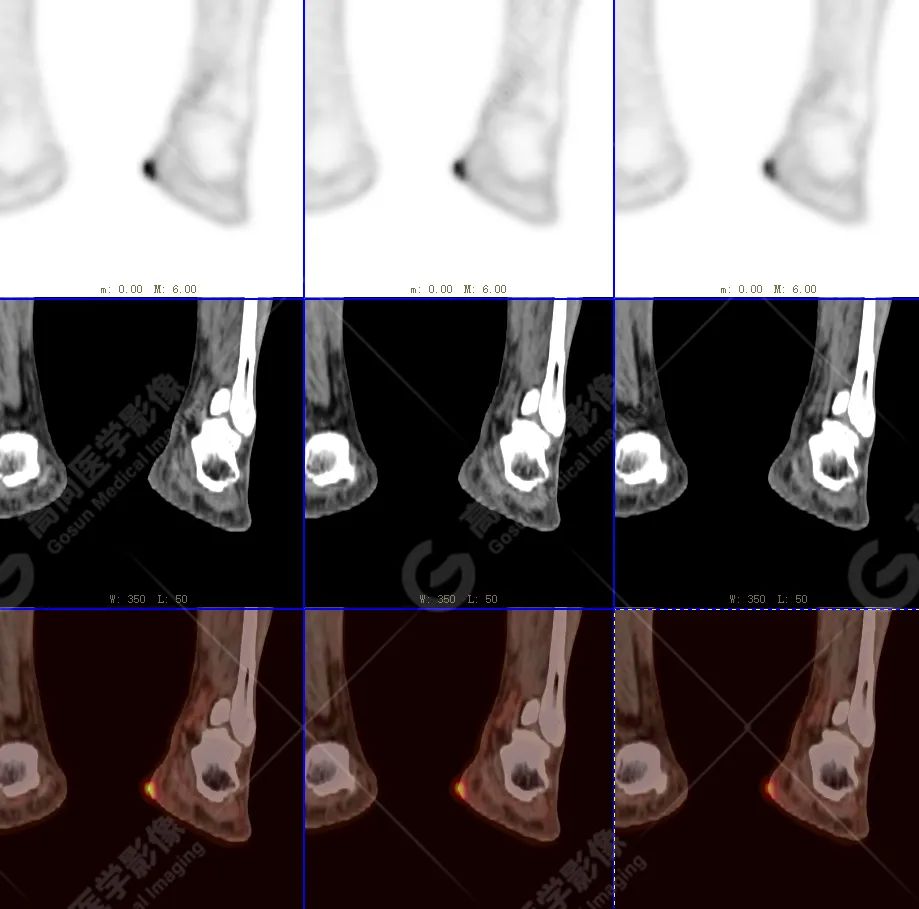

PET/CT 示:

左侧足根部内侧皮肤处见一结节状放射性摄取异常增高影,大小约 1.5 cm×1.0×1.2 cm,SUV 最大值为 7.4,CT 于上述部位见软组织增厚突起影,边界清晰,密度尚均匀,CT 值约 20 Hu,呈宽基底与皮肤相贴。

PET/CT 结论:

左侧足根部内侧皮肤结节状高代谢病灶,考虑为恶性肿瘤(拟黑色素瘤),请结合病理学;其余区域未见明显高代谢相关转移征象。

病理结果:

符合恶性黑色素瘤。